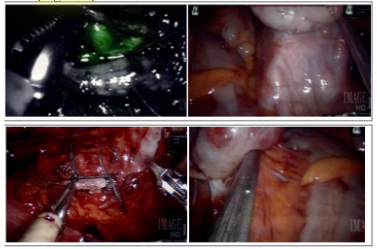

The patient underwent RASI laparoscopic surgery, consisting of total hysterectomy with bilateral salpingectomy, left ovarian vein ligation and cystoscopy (Figure 3A). Intraoperative findings included: normal uterus, fallopian tubes and ovaries. Omental and bowel adhesions to the left infundibulopelvic (IP) ligament were visualized and lysed (Figure 3B). An enlarged left ovarian vein as well as significant amount of bladder adhesions were also noted (Figure 3C).

After the left infundibulopelvic (IP) ligament was dissected out to identify the ovarian vessels, the left ovarian artery was identified with the assistance of Indocyanine green (ICG) administration (Figure 3D). The left ovarian vein was then ligated with Ethibond suture 0. Pathologic examination demonstrated congestion of large vessels and capillaries, including ectatic capillaries compatible with increased pressure (Figure 4).

Figure 3 Intraoperative laparoscopic images:

3A (top left): Single-Site Wristed Needle Driver was used. Survey after ovarian vein ligation showing hemostasis and tied sutures in place.

3B (top right): Adhesions of left ovary and the bowel

3C (bottom Left): Indocyanine Green (ICG) was used to identify the left ovarian artery

3D (bottom Right): left ovary with enlarged, engorged ovarian vessels

Our goal for surgical management was to reduce blood flow to the pelvis and thereby reduce congestion and pain. This can be accomplished by ligating large vessels (ovarian) with or without removal of the uterus and fallopian tubes. Ligation of the ovarian vein effectively cuts off circulation to the pelvis and can be done laparoscopically or by interventional radiology.7 In our case because surgery was performed endoscopically, we sutured to achieve ligation. ICG was used to assist in identification of the pelvic vasculature (Figure 3).